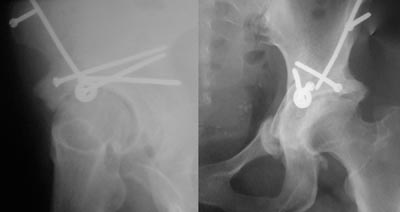

Dès lors on peut mobiliser le cotyle dans toutes les directions. On peut ainsi corriger un défaut de couverture antérieure mais aussi changer l'antéversion du cotyle et rétablir, si besoin, une meilleure balance des rotations. L’appréciation de la correction se fait à l’amplificateur de brillance: cette étape est probablement la plus complexe car il faut corriger la position du cotyle dans tous les plans de l'espace sans introduire d'hypercorrection qui pourrait être a l'origine d'autres problèmes. La stabilité primaire est obtenue par la mise en place de 3 ou 4 vis dirigées vers la colonne postérieure. La mobilisation de la hanche ne doit pas entraîner de micromouvement au niveau des traits d'ostéotomie. Il est tout à fait possible en fin d'intervention d'ouvrir l'articulation pour examiner l'intérieure du cotyle. L'intervention dure entre des mains habituées entre 75 et 90 minutes. On peut associer dans certains cas une ostéotomie du fémur pour corriger une dysplasie fémorale. Ce geste rallonge d'environ 1 heure l'intervention. |

Exemples radiographiques

| Exemple 2 | |||

![]() Jeune sportif de 35 ans avec double dysplasie fémorale et acétabulaire.

Il existe déjà des lésions articulaires importantes.

![]() Excellent résulat à 5 ans. L'amélioration de l'interligne est spectaculaire...